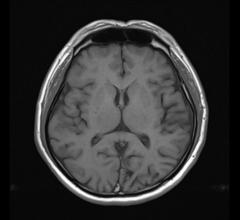

MRI creates images from the magnetic resonance created in hydrogen atoms when they are polarized and an electromagnetic pulse is used to knock them off axis. This section includes MR analysis software, MRI scanners, gadolinium contrast agents and related magnetic resonance imaging accessories.